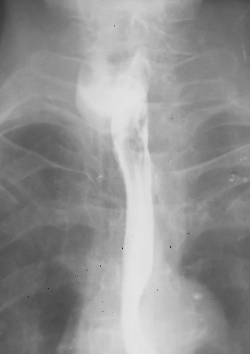

Diverticul Zenker